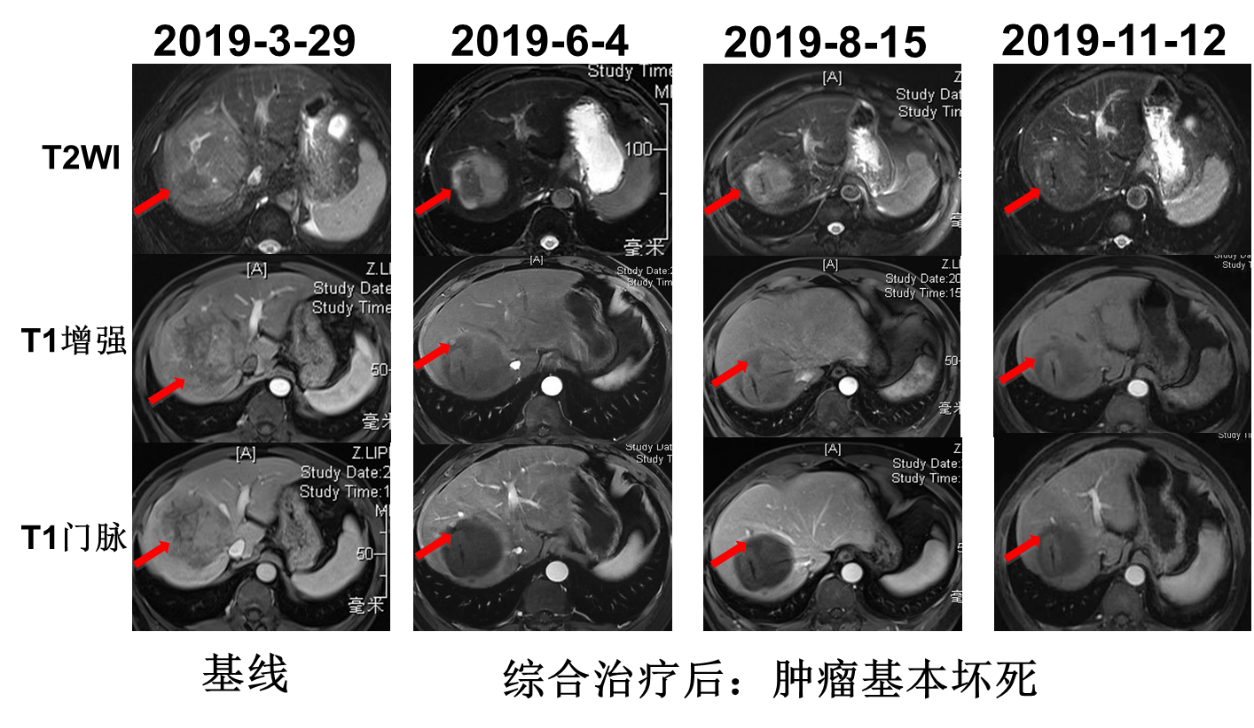

2019年4月2日行TACE+肝肿瘤微波消融术,5月6日起予以信迪利单抗治疗(200mg q3w ivgtt)联合仑伐替尼(12mg qd po),5月10日复查AFP降为正常(10.3ng/ml),PIVKA-Ⅱ降至3352 mAU/ml。6月4日复查肝脏MRI:mPR,局部强化结节,下腔静脉癌栓较前有所好转。7月2日再次行TACE术。术后于7月8日~9月16日行信迪利单抗注射4周期。8月15日复查MRI:mPR,强化结节好转,下腔静脉癌栓有所好转。8月19日复查PIVKA-Ⅱ进一步降至1202mAU/ml。11月12日复查AFP 12.4ng/ml,PIVKA-Ⅱ 1784mAU/ml,MRI提示病灶稳定。治疗经过见图2。MRI疗效评估见图3、图4、图5。

image005.png

image006.png

图5. MRI疗效评估

患者为中老年男性,既往有乙型病毒性肝炎病史及抽烟史。2019年3月MRI检查发现右肝占位。肿瘤标志物检测结果AFP为418.8ng/mL;PIVKA-Ⅱ:40208mAU/ml,结合患者病史及影像学检查诊断为肝细胞癌。肿瘤的分期对于预后以及治疗方案的制定具有重要的指导作用,肝细胞癌的分期标准比较多,常用的有巴塞罗那(BCLC)分期和TNM分期,本例患者根据巴塞罗那分期定为C期;TNM分期为T4N0M0,IIIB期。患者的体能状态评价根据ECOG标准评分为0分;肝功能化验无明显异常,Child-Pugh 评级为A级。总体来说,患者肝脏病灶局限,无远处转移,并且体能状态以及肝功能良好,于2019年4月2日针对肝脏病灶行TACE+肝肿瘤微波消融术,术后1个月起(5月6日)信迪利单抗联合仑伐替尼治疗,5月10日复查肿瘤标志物明显降低。6月4日复查发现原病灶周边强化结节,于是再次行TACE治疗,术后继续给以信迪利单抗联合仑伐替尼治疗。2019年8月15日复查,MRI显示原病灶强化结节及下腔静脉癌栓有所好转。至11月12日,信迪利单抗治疗已10个周期,复查肿瘤标志物及MRI均提示病灶稳定。